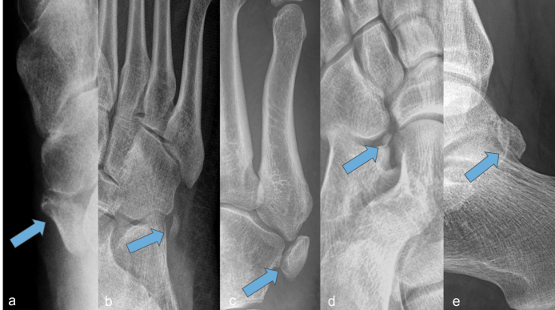

Ergebnisse: Im Röntgen zeigte sich entweder ein Os tibiale externum Typ 2, Os peroneum, Os vesalinum, Os calcaneus secundarius oder Os trigonum. In der MRT-Bildgebung fand sich ein perifokales Ödem sowie eine Tendinose mit Tendovaginitis bei 8/14 Pat. Nach konservativen Maßnahmen waren 3/14 Pat., nach zusätzlicher Infiltrations- und Stoßwellentherapie 4/14 Pat. beschwerdefrei, 1/14 Pat. zeigte eine mäßige Besserung. Nach Exstirpation des Os calcaneus secundarius zeigte 1/14 Pat. einen vollständigen Rückgang der Symptome. Nach Ossikelextripation mit Sehnenrekonstruktion wurden 4/14 Pat. beschwerdefrei, während 1/14 Pat. unter Belastung weiterhin leichte Schmerzen beklagte.

Abbildung 1 [Abb. 1]